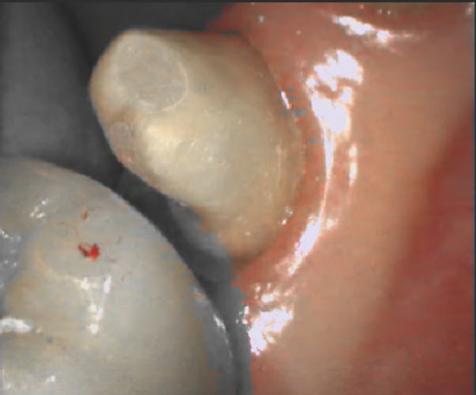

📌Patient Intraoral Condition

Before intraoral scanning, check the patient’s oral condition. Excessive blood or saliva can affect the scan data, so blood and saliva must be removed prior to scanning.

Since the intraoral scanner captures the oral condition as it is, gingival isolation is required in cases with subgingival margins or unclear margins to ensure accurate margin data acquisition.

Common isolation methods include gingivectomy using a laser or the use of cord.

| Improper Oral Environment | Proper Oral Environment |